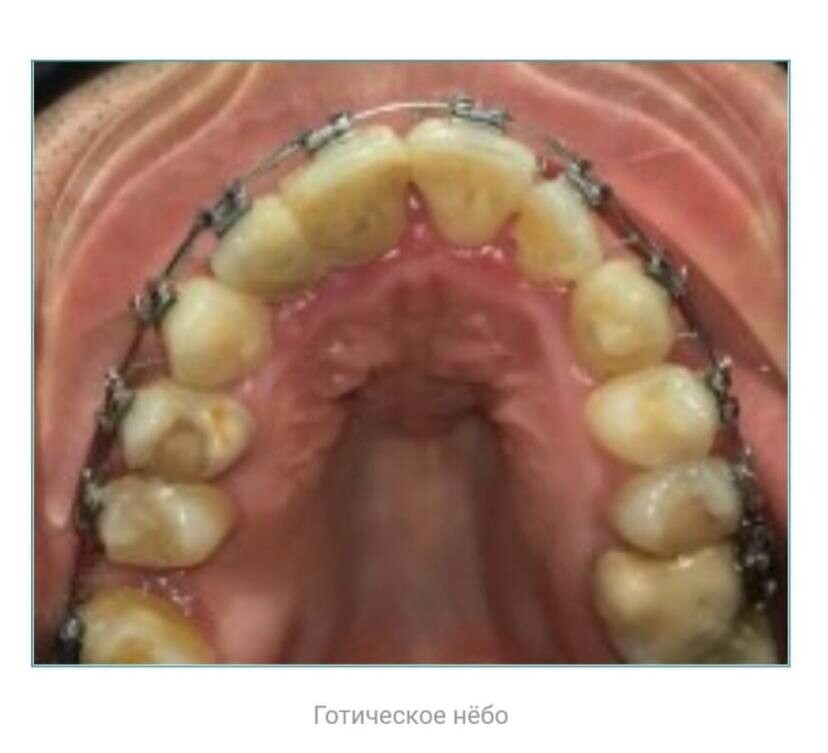

Ортодонты могут успешно расширять брекетами зубной ряд, чтобы зубам стало просторнее, но при этом небо остается готическим, а максиллы уходят вглубь

и вниз, лицевой череп сужается и вытягивается, лицо скелетизируется.

Потому что расширить зубной ряд это не то же самое, что расширить челюсть.

✅ Готическое нёбо (узкое и сводчатое) – это аномалия развития верхней челюсти, характеризующаяся высоким аркообразным сводом твердого неба. Высокий небный свод препятствует полноценному грудному вскармливанию ребенка, затрудняет носовое дыхание, вызывает нарушения звукопроизношения, может способствовать развитию аномалий зубных рядов, синдрома сонных апноэ. В настоящее время, в силу самых разных причин

от экологии до образа жизни такое небо, либо его вариации, встречается очень часто.

Представьте себе зонт - трость. Если его купол прикрыть - он выглядит узким и длинным🌂

Если же зонт раскрыть до конца ☂️ - его свод расширится, но станет коротким

и объемным. То же самое происходит с небом.

При правильном воздействии небо как бы опускается и расширяется, становится не таким глубоким и более пологим, каким и должно быть в норме.